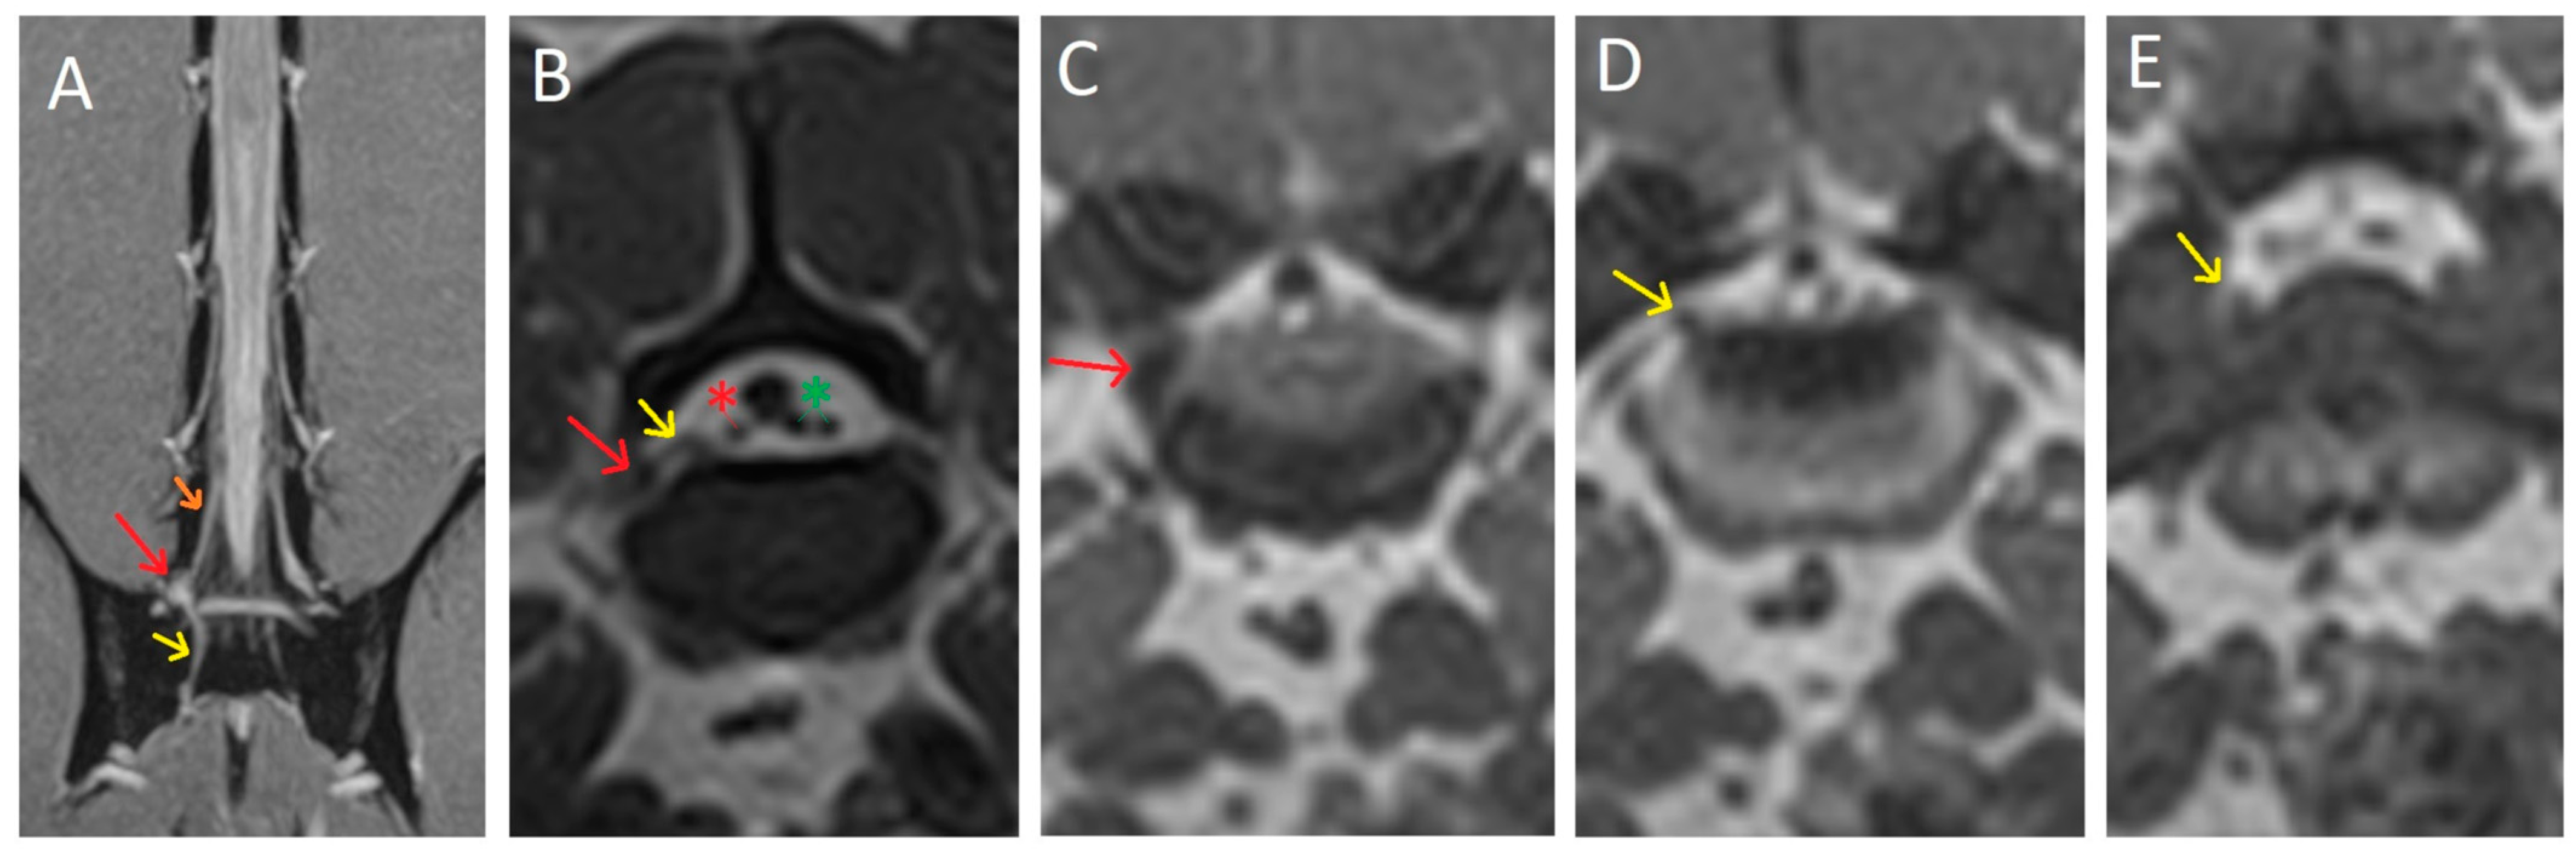

2. Case Description